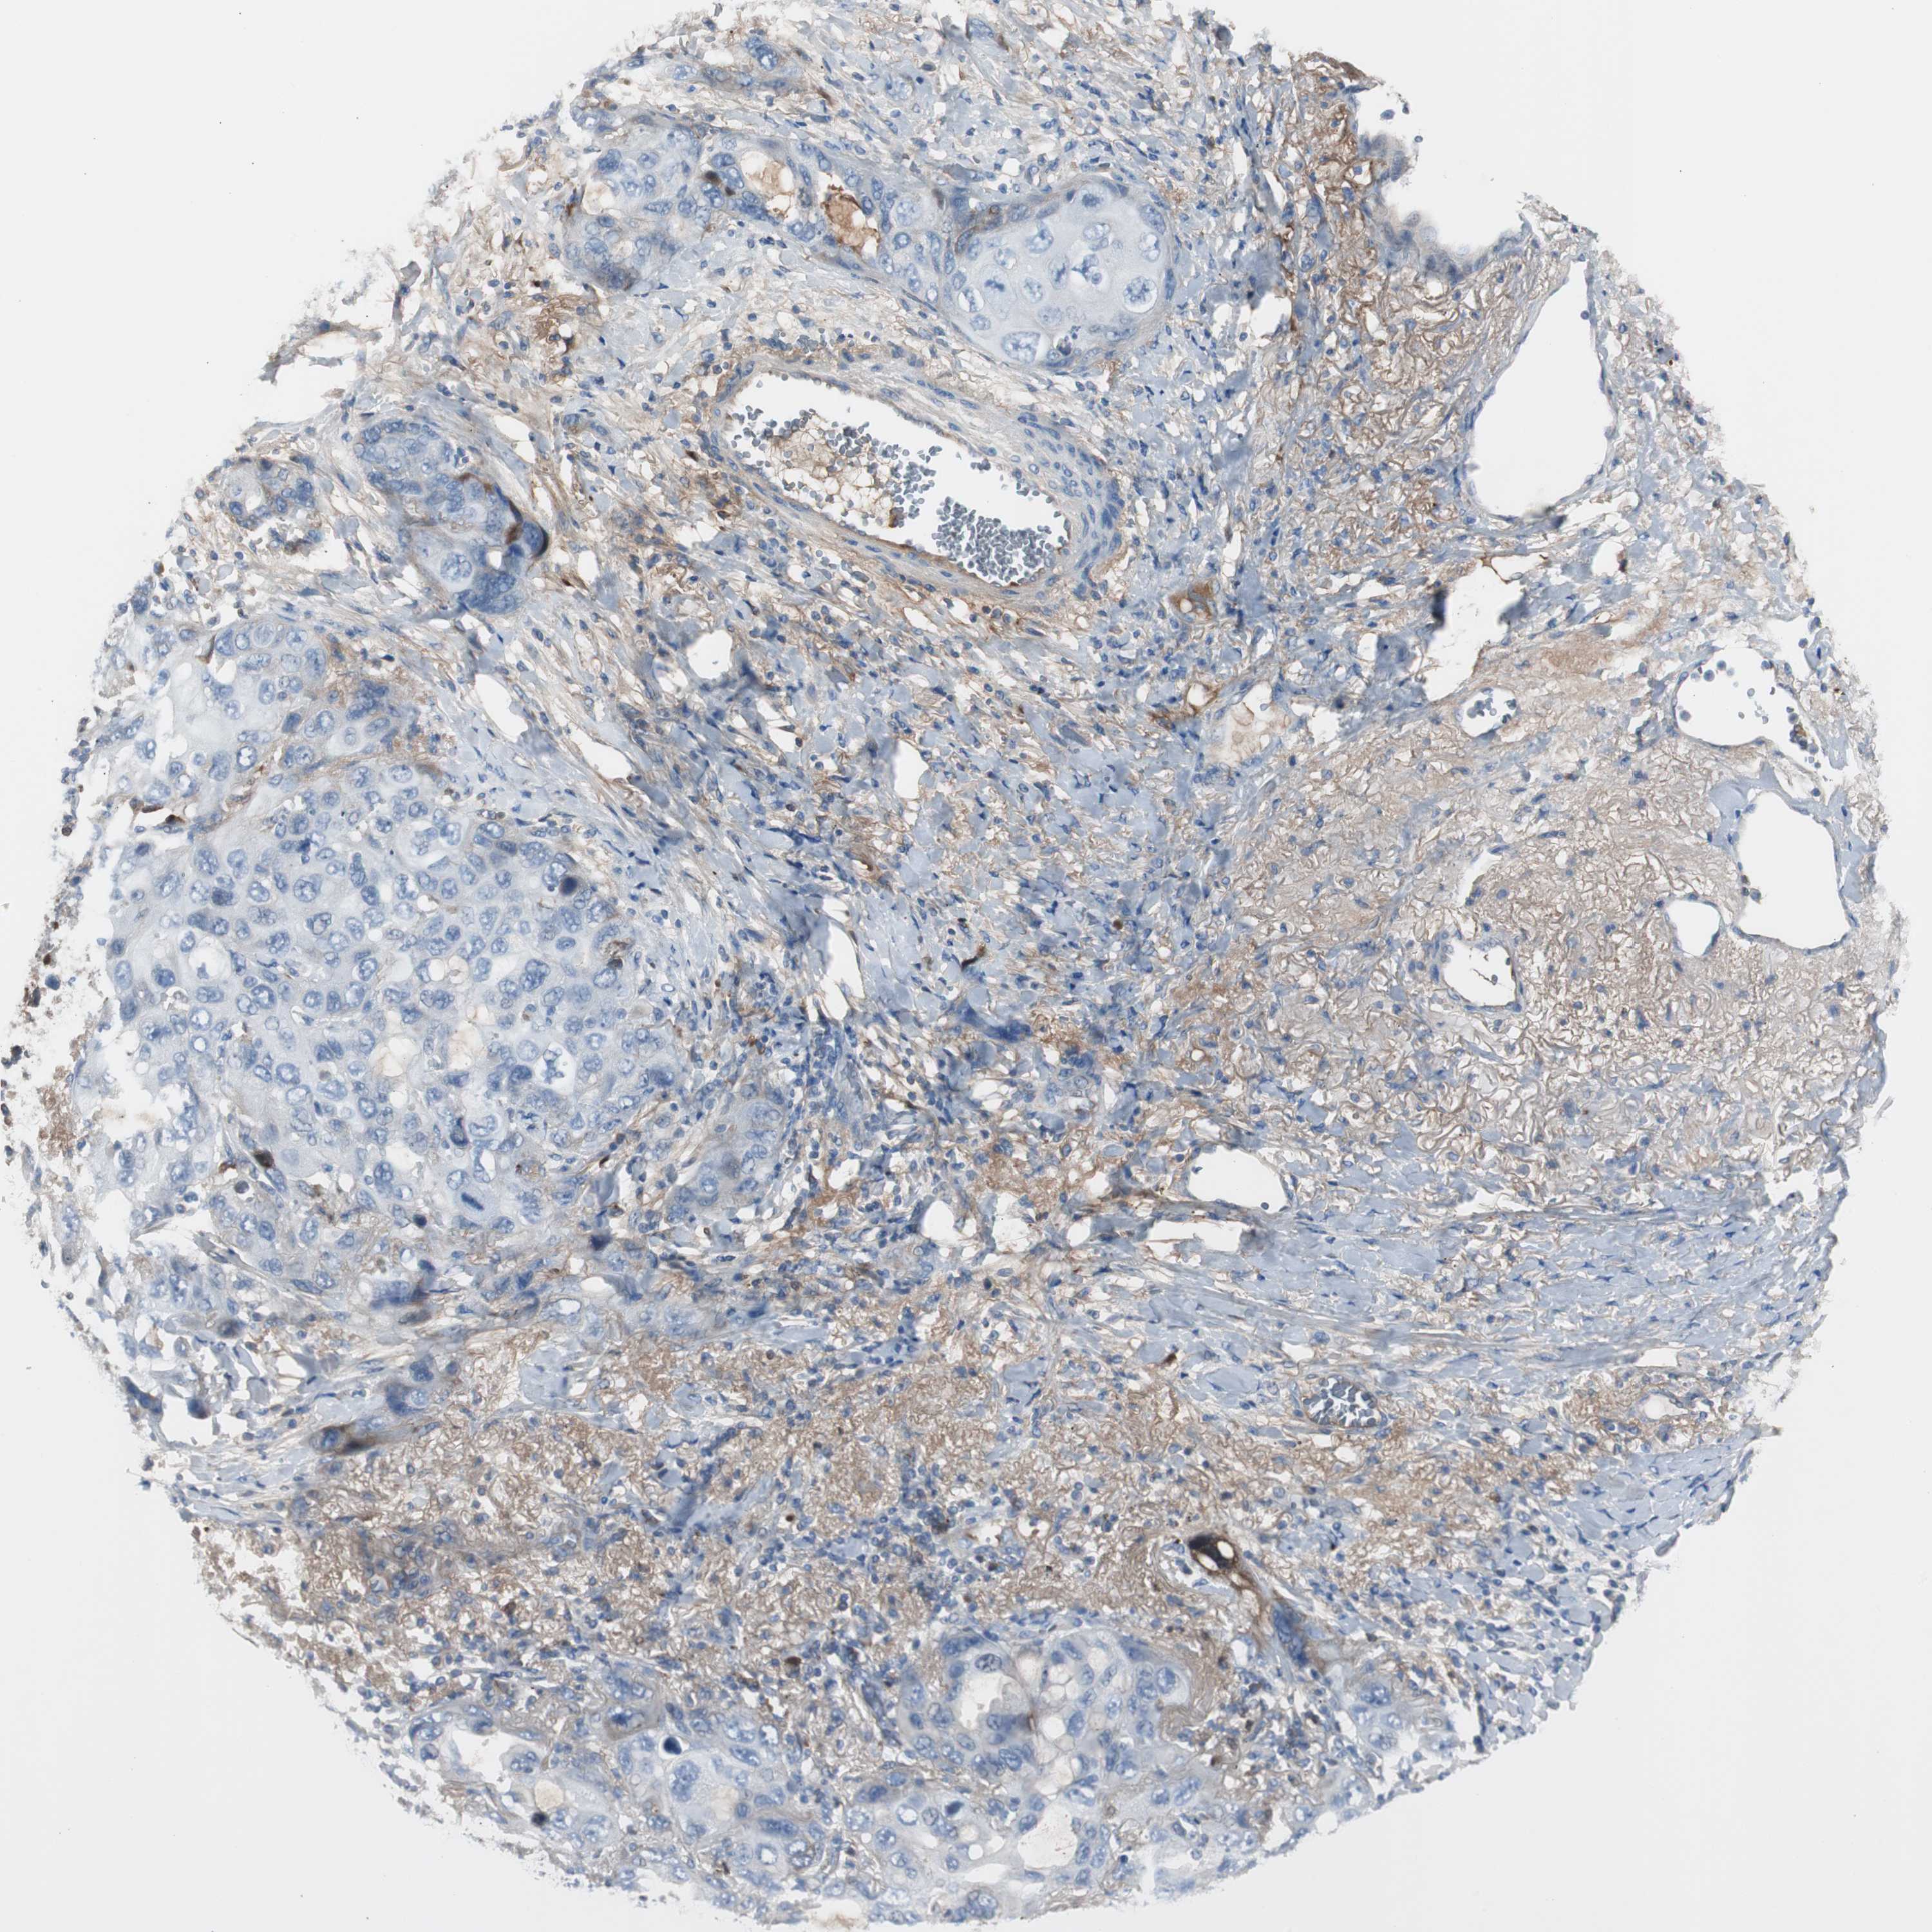

LUNG SQUAMOUS CELL CARCINOMA (TCGA) - Interactive survival scatter ploti

The Survival Scatter plot shows the clinical status (i.e. dead or alive) for all individuals in the patient cohort, based on the same data that underlies the corresponding Kaplan-Meier plots. Patients that are alive at last time for follow-up are shown in blue and patients who have died during the study are shown in red.

The x-axis shows the expression levels (FPKM) of the investigated gene in the tumor tissue at the time of diagnosis. The y-axis shows the follow-up time after diagnosis (years). Both axes are complimented with kernel density curves demonstrating the data density over the axes. The top density plot shows the expression levels (FPKM) distribution among dead (red) and alive patients (blue). The right density plot shows the data density of the survived years of dead patients with high and low expression levels respectively, stratified using the cutoff indicated by the vertical dashed line through the Survival Scatter plot. This cutoff is automatically defined based on the FPKM cutoff that minimizes the p-score. The cutoff can be changed by dragging the vertical line or by entering a cutoff value in the square labeled "Current cut-off".

Under the Survival Scatter plot the p-score landscape (black curve; left axis) is shown together with dead median separation (red curve; right axis). Dead median separation is the difference in median mRNA expression between patients who have died with high and low expression, respectively. It is calculated as follows: median FPKM expression of dead patients with high expression - median FPKM expression of dead patients with low expression. This is intended to aid the user in visually exploring custom cutoffs and the associated p-scores and dead median separation.

Individual patient data is displayed and can be filtered by clicking on one or more of the category buttons on the top of the page. Categories describing expression level and patient information include: high, low, alive, dead, female, male and tumor stages. The scale of the x-axis can be toggled between linear and log-scale by clicking on the "x log" button. Mouse-over function shows TCGA ID, patient information and mRNA expression (FPKM) for each patient.

& Survival analysisi

Kaplan-Meier plots summarize results from analysis of correlation between mRNA expression level and patient survival. Patients were divided based on level of expression into one of the two groups "low" (under cut off) or "high" (over cut off). X-axis shows time for survival (years) and y-axis shows the probability of survival, where 1.0 corresponds to 100 percent.

SERPINF1 is not prognostic in Lung Squamous Cell Carcinoma (TCGA)

Best expression cut offi

Based on the FPKM value of each gene, patients were classified into two groups and association between prognosis (survival) and gene expression (FPKM) was examined. The best expression cut-off refers the FPKM value that yields maximal difference with regard to survival between the two groups at the lowest log-rank P-value. Best expression cut-off was selected based on survival analysis .

When clicking on this number, the vertical dashed line indicating cut-off, the interactive survival plot, and the Kaplan-Meier curve will be adjusted to show results based on the best expression cut-off.

: 80.93

P scorei

Log-rank P value for Kaplan-Meier plot showing results from analysis of correlation between mRNA expression level and patient survival.

N/A

TCGA RNA samplesi

RNA-seq data is reported as average FPKM (number Fragments Per Kilobase of exon per Million reads), generated by the The Cancer Genome Atlas (TCGA) .

Normal distribution across the dataset is visualized with box plots, shown as median and 25th and 75th percentiles. Points are displayed as outliers if they are above or below 1.5 times the interquartile range. FPKM values of the individual samples are presented next to the box plot.

Average pTPM 181.6

Number of samples 489